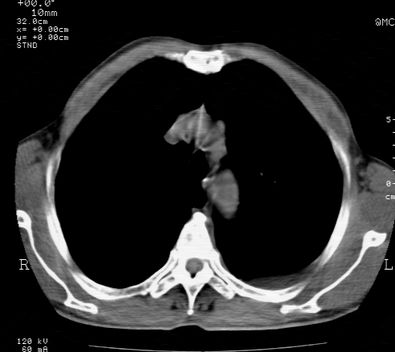

标题: CT24000:M65,胸痛,胸闷月余,既往慢支,肺气肿,肺心病 [打印本页]

标题: CT24000:M65,胸痛,胸闷月余,既往慢支,肺气肿,肺心病

左肺门肿块,相应支气管闭塞,左肺上叶、舌叶大片及散在高密度影,部分呈不张改变,两肺纹粗乱,左侧胸腔积液。考虑左侧中央型肺癌伴阻塞性改变。

左肺门见巨大软组织肿块影,直径约--,境界清,左上肺叶支气管变窄,左上肺舌叶见大片状密实影,余肺纹理增多、紊乱、纤细、部分网格状,两肺透亮度增高,纵隔内见增大多发淋巴结影,心影略左偏,左侧少量胸腔积液。

左侧中央型肺癌伴左上肺舌叶不张、纵隔淋巴结转移,左侧少量胸腔积液。